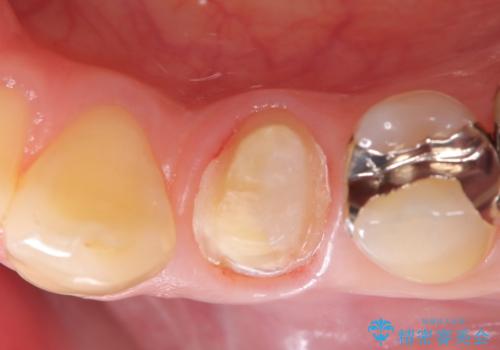

- 初診時に金属の下に虫歯があることを指摘しました。もともとの詰め物の形と虫歯の大きさから被せものでの治療となりました。見た目、材質の説明をし、セラミッククラウンでの修復となりました。

メタルインレーが入っていたこと、う蝕が大きかったこと、頬側にHysに対してのCRがあったことを踏まえてクラウンでの修復を選択しました。